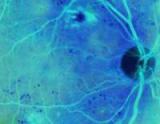

Учёные из исследовательского института глаза в первый раз регенерировали большие площади повреждённой сетчатки и улучшили зрительную функцию, используя стволовые клетки кожи (IPS cells).

Результаты исследований обещают в будущем помочь в лечении таких возрастных заболеваний, как дегенерация жёлтого пятна, пигментация сетчатки, диабетическая ретинопатия и другие заболевания сетчатки, поражающие миллионы людей во всём мире...